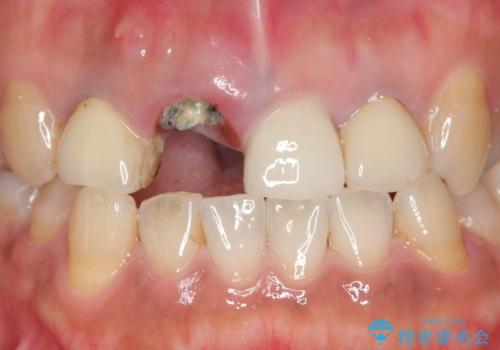

- 右上の前歯が折れてしまったので診て欲しいといらっしゃった方の症例です。

右上1番目の歯は保存不可能だったため抜歯し、ブリッジによる補綴を行いました。